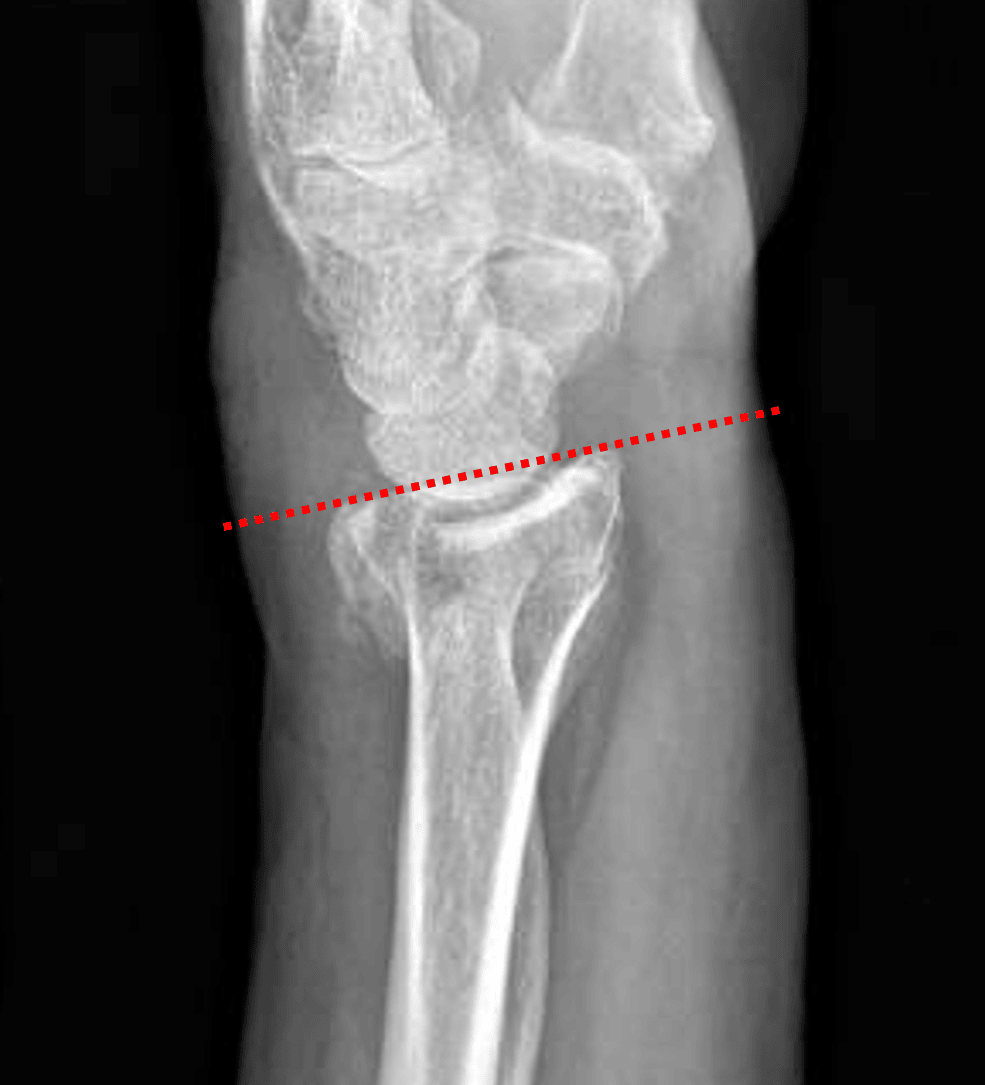

Colles fracture: lateral view shows mild dorsal tilt of the distal radial articular surface (red dotted line).

- Acute nondisplaced, mildly impacted transverse fracture of the distal radial metaphysis with mild dorsal tilt and intraarticular extension

Colles fracture (Frykman IV)